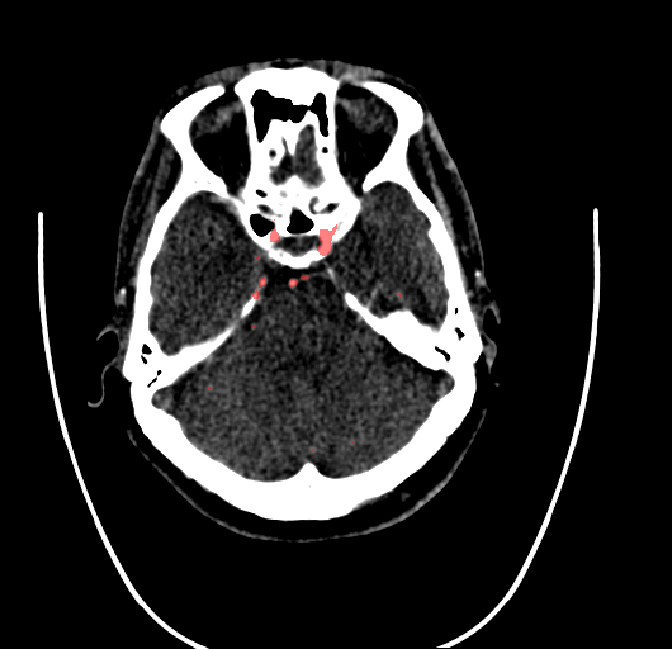

After fine-tuning, the two pre-train conditions appear to have little or no difference in terms of qualitative performance at the vessel segmentation task. However, when compared to the models trained only on real data, there are noticeable differences. Throughout Figures 4.3-4.9, the model pre-trained on scans with original CT noise is to be taken as representative of segmentation performed by the Perlin noise pre-training condition. Images showing the hand-labeled ground truth, as well as the unlabeled slice, are presented for comparison.

Figure 4.4: Segmentations on regions near internal carotid arteries. Unaltered image (left). No pretrain model (mid-left). Fine-tuned model (mid-right). Hand-labeled ground truth (right).

For vessels in the center of the head, all model types appear to accurately segment vessels. In certain cases, the models appear to learn to correctly avoid segmenting pieces of bone that could, in terms of shape and contrast, easily be confused with large vessels. An example of this can be seen in the frontal section of Figure 4.6.

The models appear to have a hard time segmenting vessels close to the skull surface. The model trained exclusively on patient data appears to struggle far more for these types on conditions than the fine-tuned models. Figure 4.8 shows an example of the fine-tuneds model having close to no trouble segmenting vessels near the left side of the skull, while the baseline model suffers heavily from false negatives. To lesser degree, this effect can also be observed in the frontal lobe of Figure 4.9 In the other hand, Figure 4.7 presents an example of both models failing to segment vessels near the top of the skull.

In the other hand, it should be noted that fine-tuned models suffered from false positives more often than models with no pre-training. The fine-tuned models appeared to occasionally segment regions near the skull, which although similar in intensity to vessels, had no resemblance in terms of shape. Examples of this are seen in Figure 4.4 near the occipital bone and near the right temporal bone. Examples of oversegmentation were observed to happen commonly around the internal carotid arteries. This is likely due to the amount of contact surface between the artery and the surrounding bone. There was also a tendency for all model conditions to segment bone regions that were similar in shape to large vessels (Figures 4.3 and 4.4). Bone structures in such regions have similar pixel intensities to the arteries transporting contrast material, which could explain the source of confusion for a model.